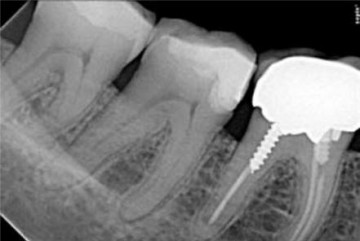

Preoperative x-ray of a patient’s necrotic 47 which received a crown reconstruction 6 months ago (glass ionomer cement + composite).

Postoperative x-ray after shaping with 2Shape, apical finishing using F40 and obturation with pure thermomechanical condensation technique thanks to Revo Condensor.